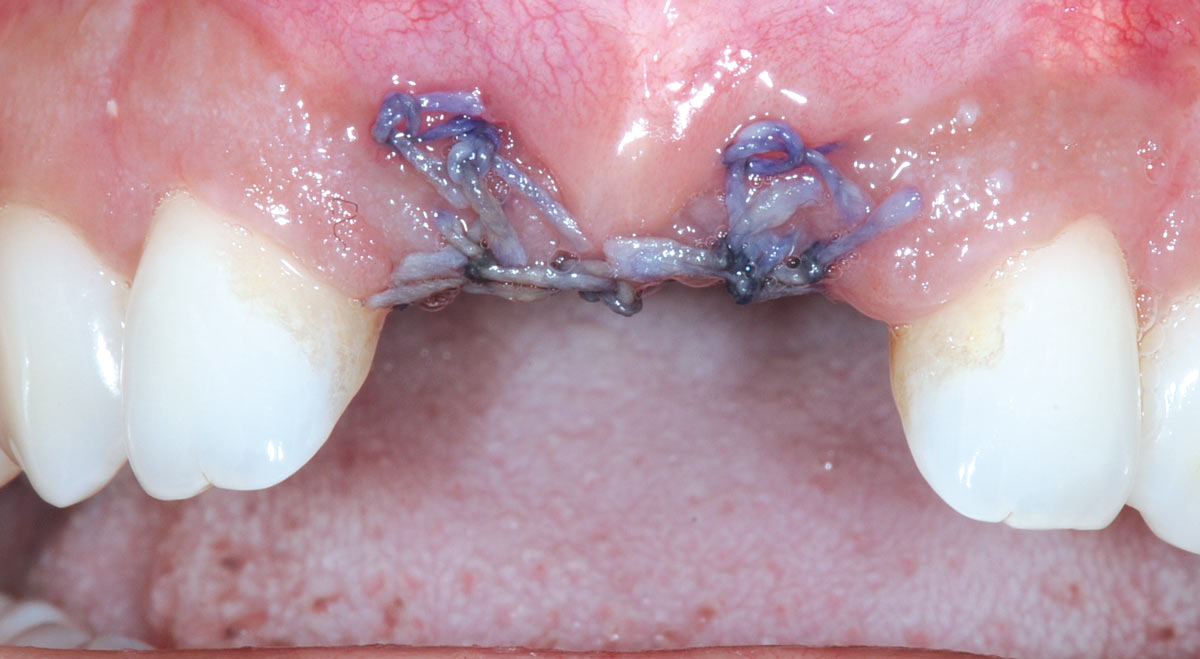

18/26 - Sutured free of tension with vycrilBone augmentation in aesthetic zone with maxgraft® bonering - Dr. A. Patel